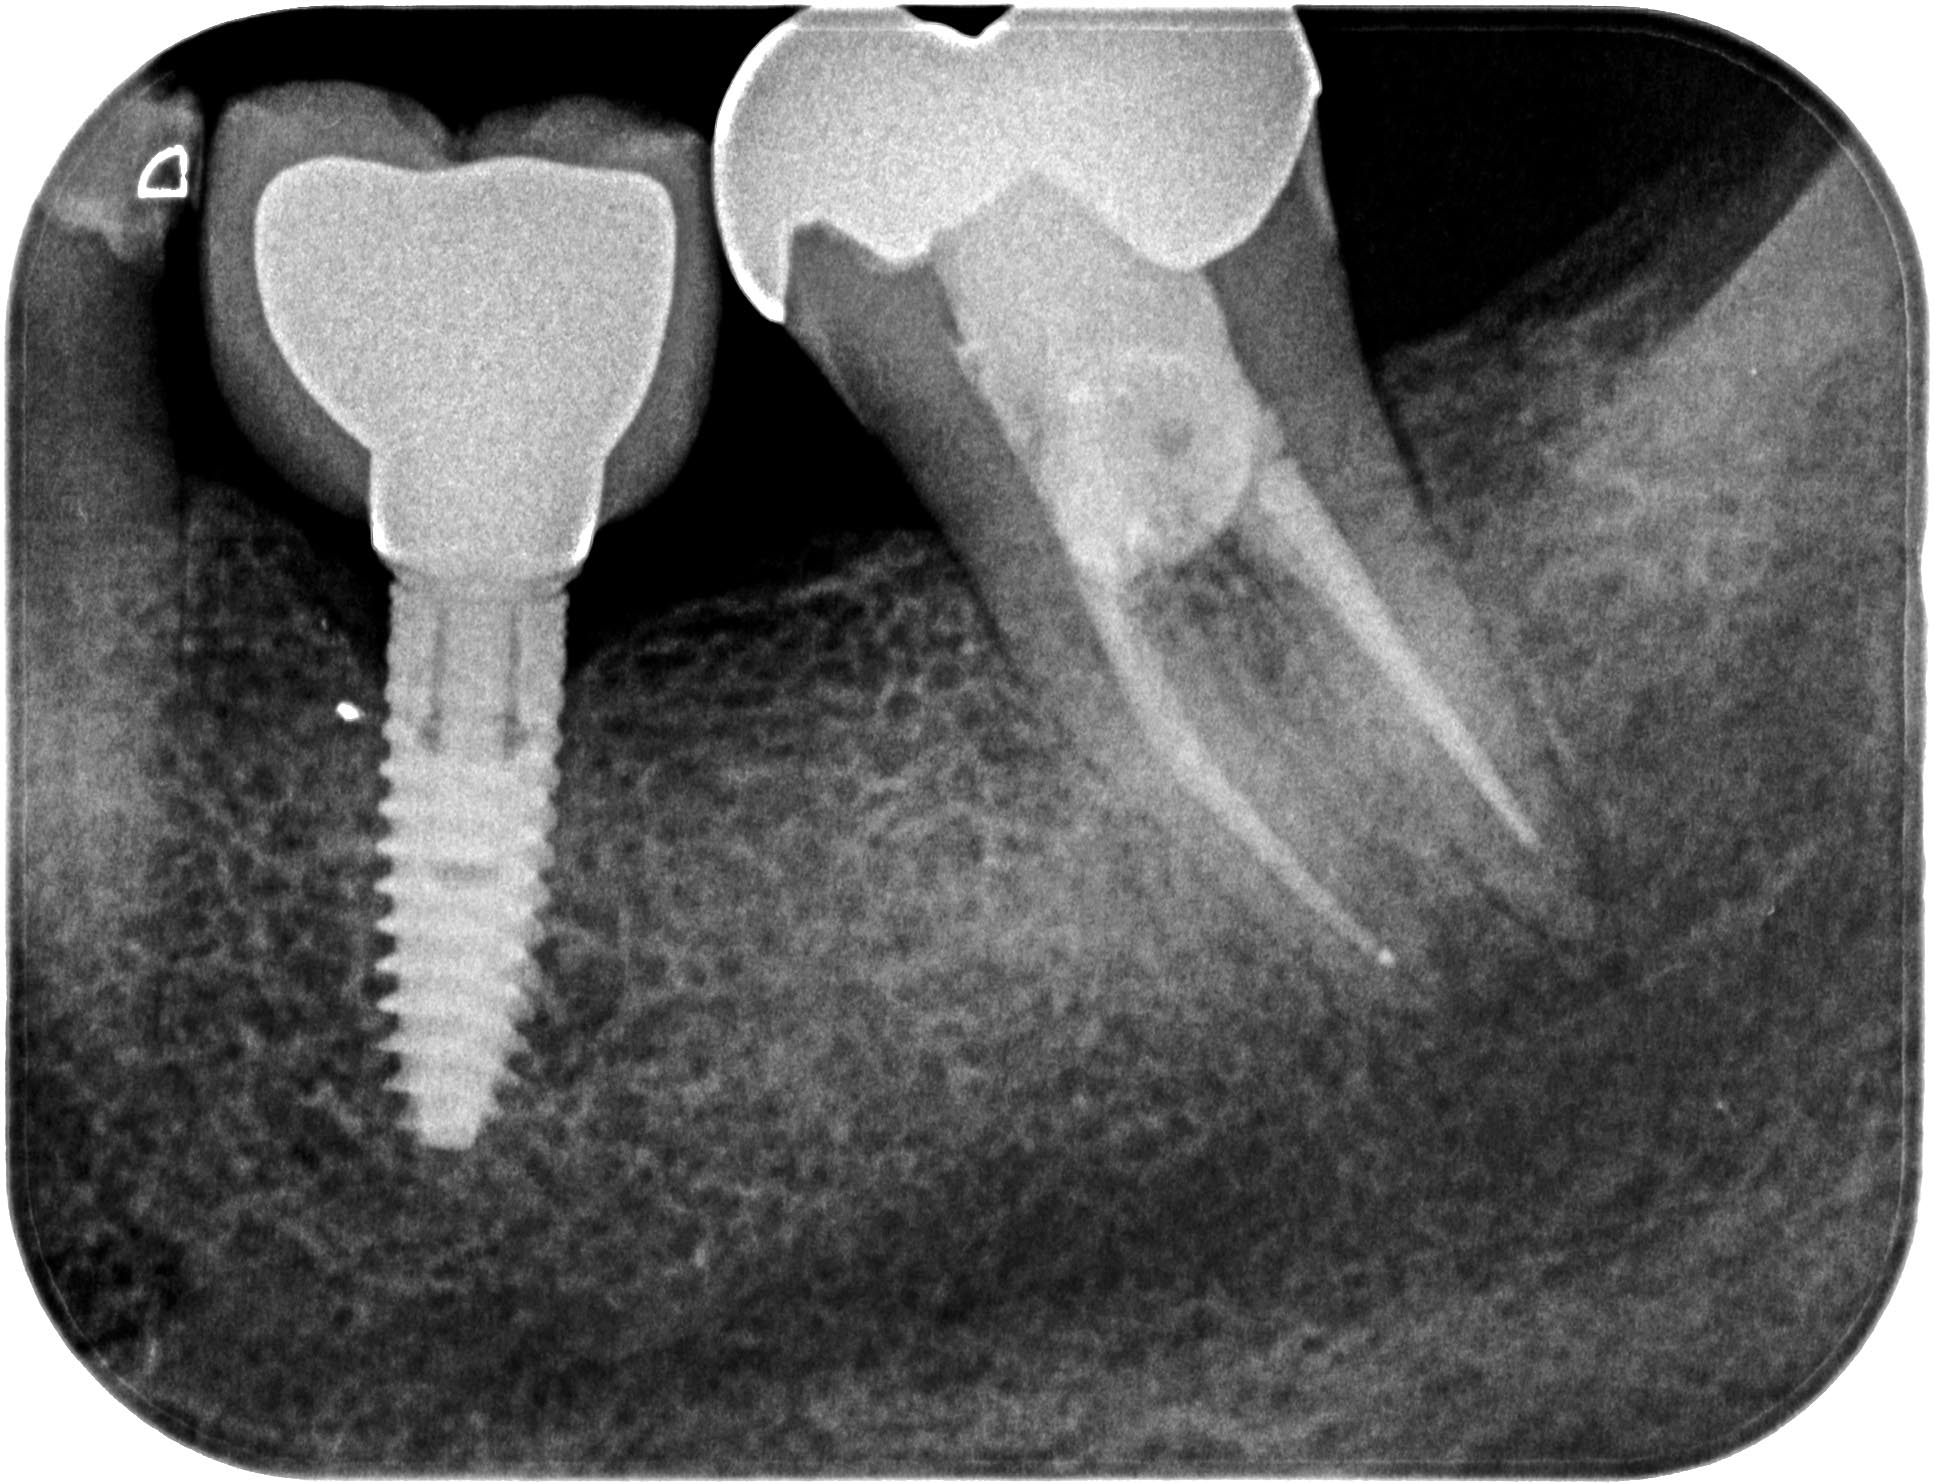

Distal-5 Veröffentlicht 16. Mai 2016 am 1935 × 1483 in Starker distaler Knocheneinbruch – Lohnt der Versuch eines Zahnerhaltes ? Zahn 37 7 Monate post WF Mai 2015